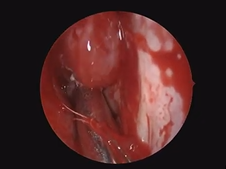

Retrosigmoid Approach for Resection of Vestibular Schwannoma with Hearing Preservation

- Date : 01/01/2020